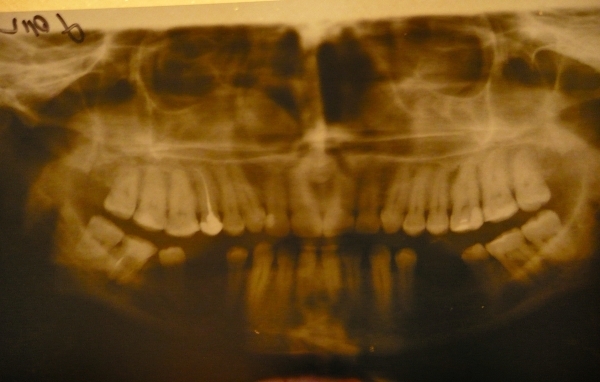

У меня мезиальный прикус. Ортодонты моего города рекомендуют остеотомию.

Очень хотелось бы сначала остеотомию, а потом уже носить брекеты, т.к. подготовка брекетами для меня сейчас неподъемна.

К сожалению, что касается скорейшего ортодонтического лечения после операции, я Вам ничего нового не скажу. Необходимы снимки и очный приём.